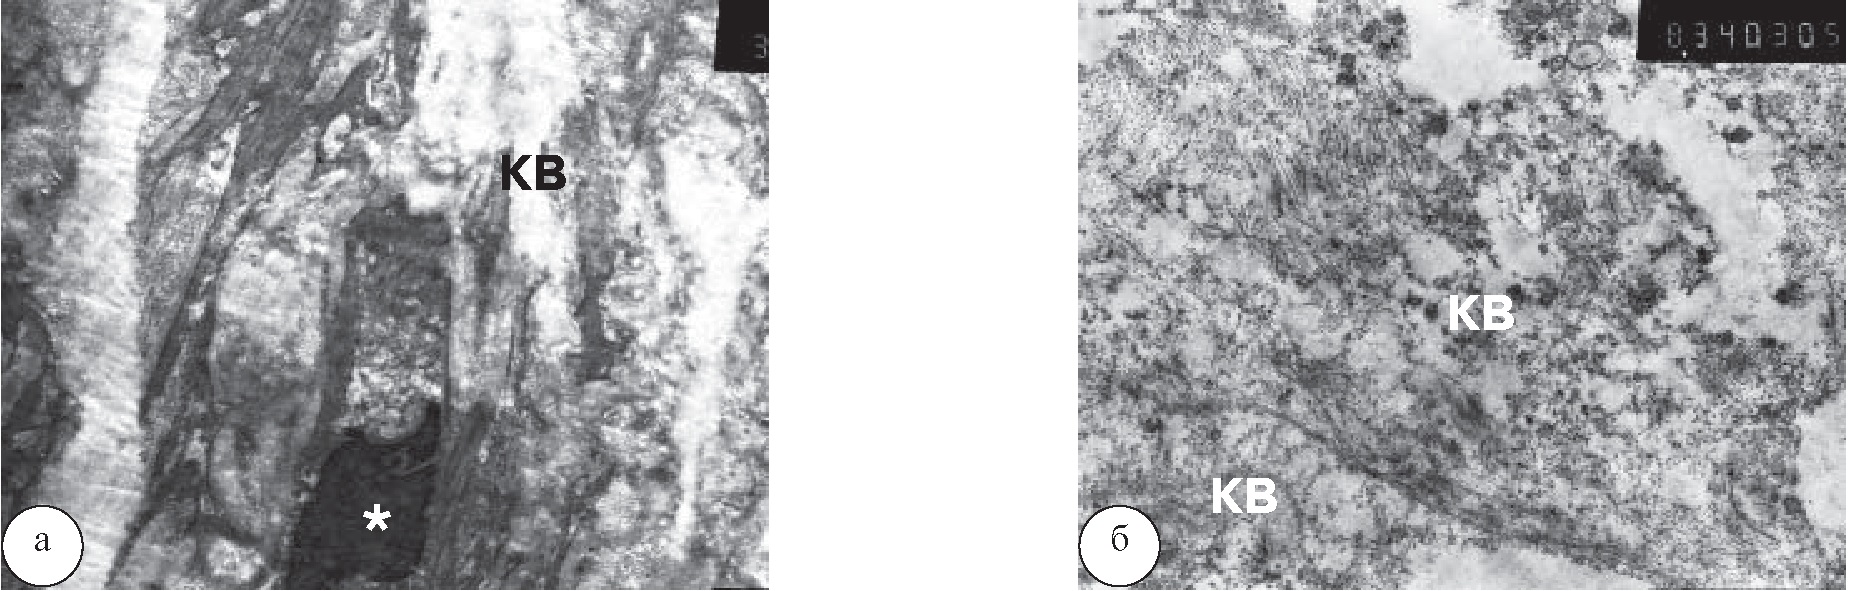

Рис. 5. Ядра клеток в состоянии апоптоза: а – измененные фибробласты (*) и разрушенные пучки коллагеновых волокон (КВ), ув. ×3300; б – тонковолокнистый неструктурированный коллаген (КВ), ув. ×6600

Рис. 6. Изменения в строме клеток поджелудочной железы: а – вакуолизация стромы ПЖ с хаотическим расположением коллагеновых волокон (КВ), ув. ×3300; б – гранулярный, сильно измененный осмиофильный коллаген (КВ) в почти пустом пространстве ПЖ, ув. ×6600